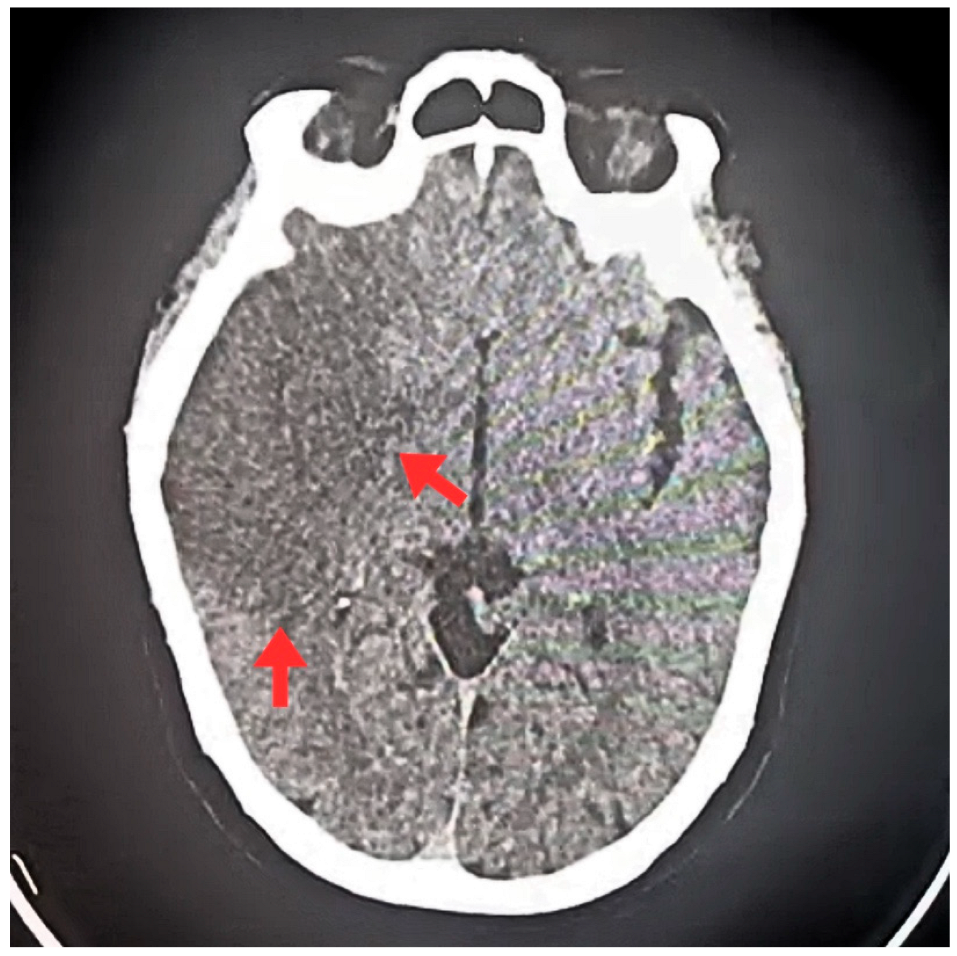

| T0 + ED arrival | Emergency Dept. | Stroke code activated. NIHSS 9, GCS 11/15, premorbid mRS 0. | ECG: typical atrial flutter with rapid ventricular response. Non-contrast CT brain: right MCA ischemic stroke (ASPECTS 7), no hemorrhage. | Supportive acute stroke care | Acute ischemic stroke suspected/confirmed |

| First 24 h | Hospital | Hemodynamic and neurological stability. | Follow-up CT: no hemorrhagic transformation. | Continue monitoring/management | No bleeding complications documented |